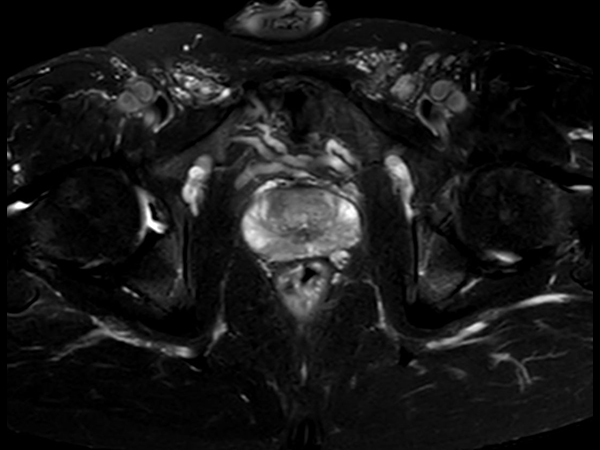

For prostate exams, the MSK M coil can be used in combination with the posterior coil, delivering exceptional quality MR images and high patient satisfaction.

Premium signal-to-noise ratio is achieved via dStream, providing outstanding image resolution.